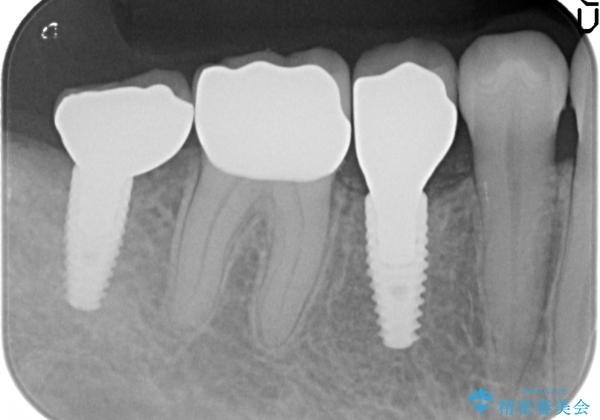

- 右下の奥歯の被せ物が外れてしまったので診て欲しいといらっしゃった方の症例です。

右下7は欠損しており、右下5は保存不可能だったため、インプラントによる欠損補綴を行いました。

インプラント埋入時には骨が不十分な部位に骨増生を行っております。